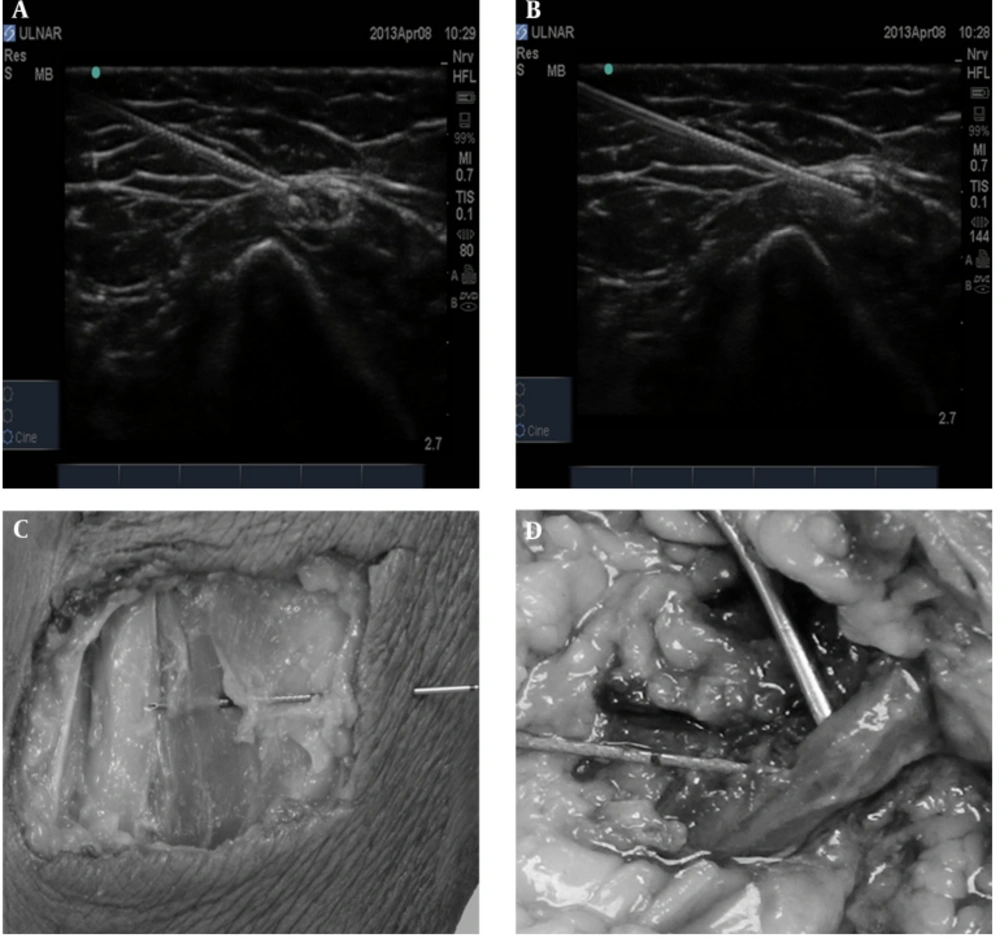

All of the cadaveric tissues were obtained and utilized in accordance with the Human Tissue Act (2004), which includes first person consent for cadaveric investigation. Cadaveric preservation involved the use of phenol and glycerol rather than formaldehyde, which allowed similar tissue mobility as in vivo conditions. A total of 60 injections were conducted using 12 cadaveric arms from six cadavers. Five cadavers were initially provided to perform bilateral radial, median, and ulnar nerve injections (30 intraneural and 30 perineural). In one cadaver, the radial nerve could not be identified on one side and in another one, an ulnar nerve injection measurement was missed due to investigator’s error. As such, an extra cadaver was used to complete the sixty injections. In total, 20 injections were conducted for each of the radial, median, and ulnar nerves (10 intraneural and 10 perineural). All injections were performed at the level of the distal arm. Radial nerve was localized at the anterior compartment of the arm after leaving spiral groove between brachialis and brachioradialis muscle and before division into deep and superficial branch. Median nerve was identified medial to brachial artery in the antecubital fossa. Ulnar nerve lies most superficially under the skin, in compare to radial and median nerve, cranially to the medial epicondyle. An M-Turbo USG system (Sonosite-Fuji Inc, Bothell, WA, USA) was used with a linear 6 to 13 MHz transducer L-38 for needle placement. After identifying a cross-sectional view of the nerves at the described level, an 80-mm, 22-G needle (Sonoplex, Pajunk, Melsungen, Germany) was inserted using an in plane technique. The perineural injection was performed within 1 mm to the epineurium as per standard peripheral nerve block to ensure free flow of solution. For intraneural injection, the needle was inserted into the clearly identifiable nerve structure as seen on USG and according to the current understanding of the concept (3). For intraneural needle placement, once the needle passed the epineurium, USG assessment could not differentiate between extrafascicular (interfascicular epineurium, perineurium) or intrafascicular needle placement (endoneurium, axons). USG images of both perineural and extraneural needle position were captured and stored. Solution spread for perineural injection and nerve swelling (change in cross-sectional area) for intraneural injection were not recorded as a video clips due to a small volume of injection (1 mL) and with the assumption that it would not add value to the investigation. After needle placement, 1 mL of 0.9% NaCl was injected over ten seconds (0.1 mL/sec) and the opening injection pressure was recorded in psi using a Controlled Disc Stimulation (CDS) device (Controlled Disc Stimulation, NeuroTherm, Middleton, MA, USA) (Figure 1).

We defined opening injection pressure as the pressure peak that followed the initiation of the injection. Most of the injections produced a similar pattern of a low initial pressure, increasing to a maximal “peak pressure” (opening injection pressure) and ended in a lower pressure. Some injections did not reach peak value within ten-second injection time. The CDS device was utilized as it is known to deliver precise pressure recordings in provocative discography: volume accuracy of 0.05 mL, pressure accuracy of ± 5%, and flow rate accuracy of 1.1% as per Operation/Service Manual (19). The NeuroTherm CDS system employs a syringe pump that delivers media in a controlled fashion, a syringe with an integrated pressure transducer, and a piece of software that allows the calculation of the pressure at the tip of the needle by accounting for the fluid dynamic variables between the transducer and the tip of the needle. The calculated pressure is displayed on the CDS screen. Data was recorded using a computer-based data acquisition system (LabView, USA). In this study, encountered fluid dynamics were described using the Navier-Stokes equation, which took the key variables affecting fluid behavior into account. The key variables were fluid viscosity (cP), flow rate (mL/s), needle length (cm), needle gauge (ga), tubing length, and tubing diameter. To detect any difference in terms of needle length, we measured the baseline (needle open to air) pressure of injection of 1 mL of 0.9% NaCl at a rate of 1 mL in ten seconds with 22-G needles of consecutively 100-mm, 80-mm, and 50-mm lengths as these needle lengths are routinely used clinically. The tubing length was kept the same in each case. The present investigation chose the 80-mm needle as it was most commonly used in clinical practice in our institution. Peripheral nerve block of median, ulnar, and radial nerve, selectively or in combination, often follows immediately infraclavicular brachial plexus block to speed up onset in desired distribution. Needles were left in situ after completing the injection and recording of injection pressure. The cadavers were subsequently dissected to confirm needle placement. The dissections confirmed needle placement and are illustrated together with the USG images in Figure 2. All injections were performed by main investigator (AK) with more than eight years of experience in USG-guided interventions. Injection pressures were recorded on CDS device by DD (David Drew - Operator of CDS device (AK) being blinded to the needle position. All dissections were performed by MS and AV. The data was statistically analyzed using paired-samples t tests to compare the intraneural and perineural values obtained from the same nerves. Significance was assumed at P < 0.05. All statistical analyses were conducted using GraphPad (version 6, USA).

The baseline pressure of injection of 1 mL of 0.9% NaCl at a rate of 0.1 mL/sec with 100-mm, 80-mm, and 50-mm 22-G needles showed no difference in pressure values (Table 1). All of the cadaveric dissections confirmed that the needle was positioned correctly (Figure 2). The CDS graphs produced following the injection of 1 mL of 0.9% NaCl in ten seconds are displayed in Figure 3. This data shows that intraneural placed needles produced a greater injection pressures in comparison to perineural injections across all three nerves. The means of generated pressures by intraneural and perineural injections into the median nerve were respectively 29.4 ± 9.3 and 7.2 ± 2.5 (P < 0.01). The means of generated pressures in the radial nerve through intraneural and perineural injections were respectively 27.3 ± 8.5 and 8.3 ± 2.5 psi (P < 0.01). The means of generated pressures in the ulnar nerve by intraneural and perineural injections were 17.9 ± 7.0 and 6.7 ± 1.8 psi (P < 0.01) (Figure 4). All perineural injections produced a pressure of < 12 psi. In contrast, all intraneural injections pressures for median nerve and all of that for radial nerves, except one measurement, were > 20 psi. These results are illustrated in Table 2 and Figure 4.